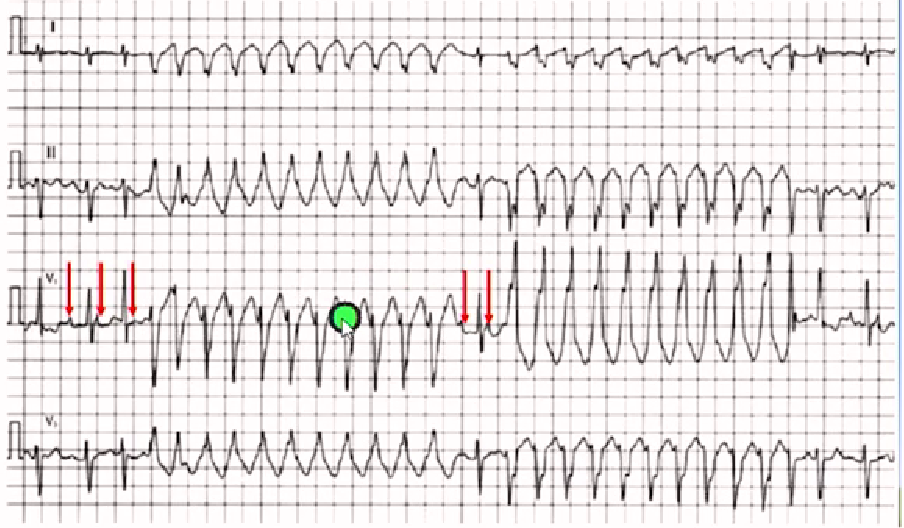

房颤伴连续差传-蝉联现象

差传与室速鉴别

房颤伴差传心电图特点

房颤长间期后出现提早(短问期)的畸形ORS波。

70%室内差传V1导联呈3相波右束支阻滞。

右束支阻滞型差传起始向量常与基本窦性心搏相同。

房颤伴差传后无长间歇多发生在快室率时易发生差传。

房颤伴室早的心电图特点

联律间期较固定;

畸形的QRS波起始向量与基本心搏不同;

室早后有较长的代偿间期;

QRS波多大于140-160ms;

既往心电图室早有利于鉴别;

常见房颤心室率缓慢时出现;

室早图形特点V1呈单相或双相,胸导联呈同向性。

房颤时室早与室内差传鉴别